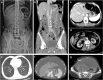

Background: Pneumatosis cystoides intestinalis (PCI) is characterized by gas-filled cysts in the intestinal submucosa and subserosa. There are few reports of PCI occurring in duodenum and rectum. Here we demonstrated four different endoscopic manifestations of PCI and three cases with intestinal stricture all were successfully managed by medical conservative treatment.

Case presentation: There are 6 cases of PCI with varied causes encountered, in which the etiology, endoscopic features, treatment methods and prognosis of patients were studied. One case was idiopathic, while the other one case was caused by exposing to trichloroethylene (TCE), and the remaining four cases were secondary to diabetes, emphysema, therioma and diseases of immune system. Of the six patients, all complained of abdominal distention or diarrhea, three (50%) reported muco-bloody stools, two (33.3%) complained of abdominal pain. In four other patients, PCI occurred in the colon, especially the sigmoid colon, while in the other two patients, it occurred in duodenum and rectum. Endoscopic findings were divided into bubble-like pattern, grape or beaded circular forms, linear or cobblestone gas formation and irregular forms. After combination of medicine and endoscopic treatment, the symptoms of five patients were relieved, while one patient died of malignant tumors.

Conclusion: PCI endoscopic manifestations were varied, and radiology combined with endoscopy can avoid misdiagnosis. The primary bubble-like pattern can be cured by endoscopic resection, while removal of etiology combined with drug therapy can resolve majority of secondary cases, thereby avoiding the adverse risks of surgery.